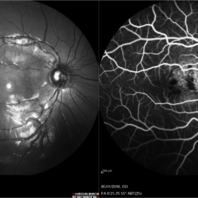

Choroidal hemangioma

Fundus photograph and FA of 14-year-old girl with macular choroidal hemangioma previously treated with PDT three years ago. Hipofluorescence are due to pigmentary changes.

Photographer: Andrea Elizabeth Arriola-Lopez, MD MSc

Imaging device: Heidelberg Engineering

Condition/keywords: choroidal hemangioma, macular changes, photodynamic therapy